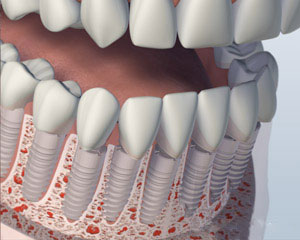

The final option is to have all your teeth individually replaced so that they will appear to be growing out of your gum tissue and will most closely resemble the appearance of your natural teeth. This option usually requires eight or more implants. Separate abutments or support posts for each one of these implants will be made and crowns for each missing tooth will be placed. The teeth are often joined together for sinus grafting to replace bone height strength and support. Overall, this is the most costly option, because it requires the most implants and individual replacement tooth fabrication. Your replacement options may also be limited by the current size and shape of your jaw bone.

1. Before

2. Implants Placed

3. Denture Attached